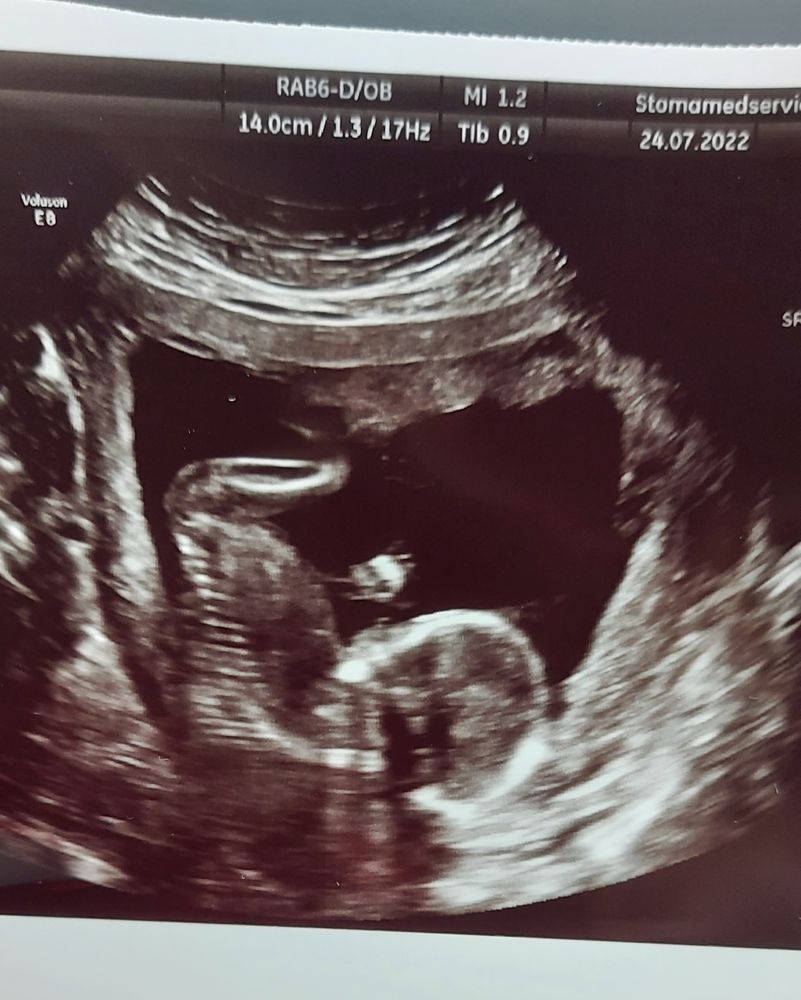

Узи 16 недель

Тут человек рукой всем машет🥰

На первом скрининге там такой активности не было,сейчас в животе целая вечеринка,а я этого даже пока не чувствую. Надеюсь н